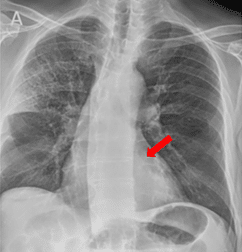

Clinical studies have evaluated the ability of spectral chest radiography to visualize coronary artery calcium.

Clinical evaluations comparing spectral radiography images with traditional X-ray have suggested:

- Opportunistic visualization of CAC and valve/vascular calcium with up to a 61.8% increase in sensitivity compared to standard X-ray, and an AUC of 91% relative to low dose CT¹⁰

Coronary artery calcium becomes visible in the SpectralDR bone image and is confirmed on CT.